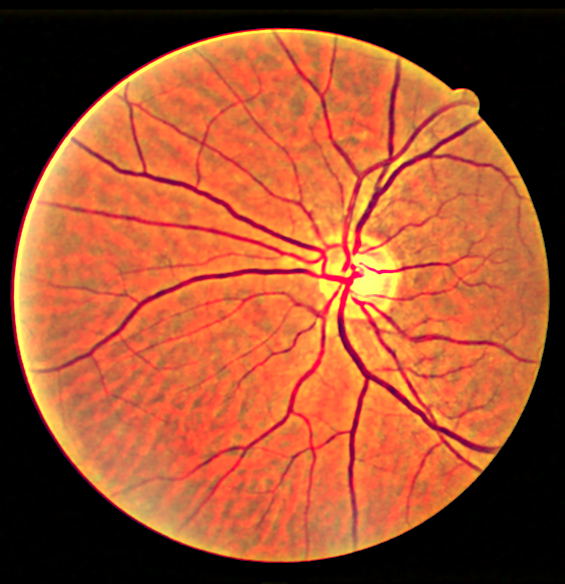

Some more examples for different images, and outputs compared against CLAHE

First column: Original images

Second column: CLAHE corrected images

Third column: Proposed results